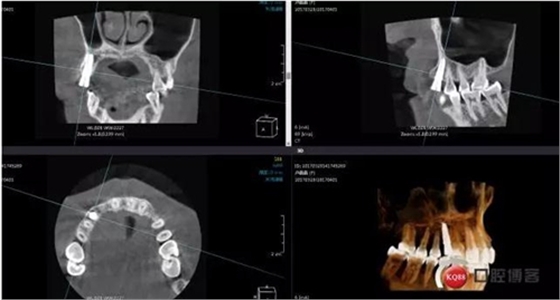

患者右上二缺失,CT示唇腭向骨量不足,右上3為乳牙滯留且骨量足設(shè)計(jì)右上三即拔即種手術(shù)